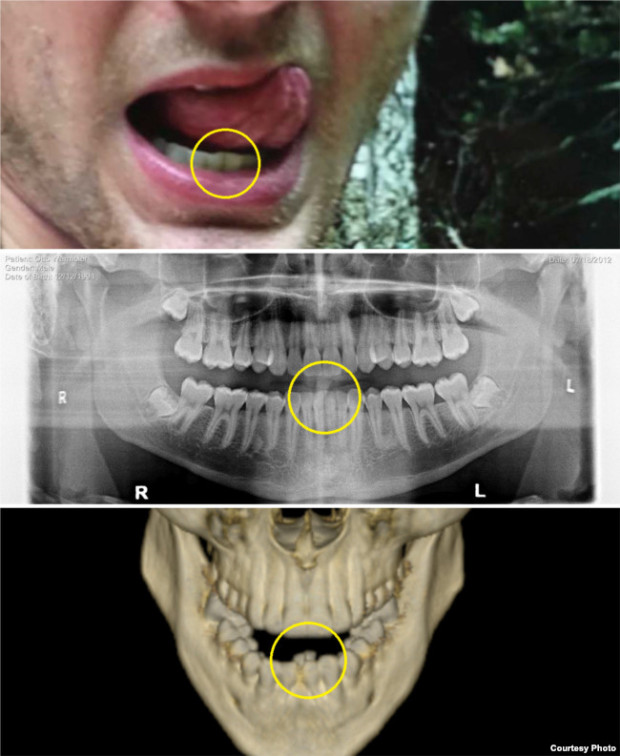

웜비어의 주치의였던 대니얼 캔터 박사는 재판부에 제출한 서면 진술서를 통해 ‘웜비어의 사인은 뇌 혈액 공급이 5~20분간 중단되거나 크게 줄었기 때문”이라면서, 북한 측이 주장했던 식중독의 일종인 ‘보툴리누스균’ 증상이 웜비어에게 발견되지 않았다고 지적했다.

아울러 북한에서 촬영된 뇌 촬영 사진을 근거로 웜비어의 뇌 손상 시점을 2016년 4월로부터 수주 전으로 예상해, 억류 기간의 상당 부분을 병상에서 보냈다는 점을 암시했다.